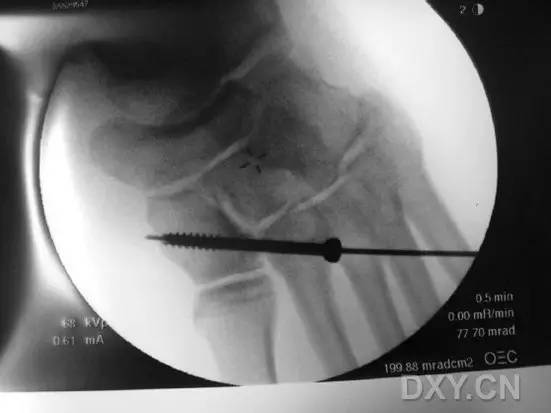

这一损伤的传统固定方式是将 1 枚螺钉(以下简称为 Lisfranc 螺钉)经内侧楔骨向第 2 跖骨基底置入(图 1)。

图 1. 传统的 Lisfranc 螺钉置入方法